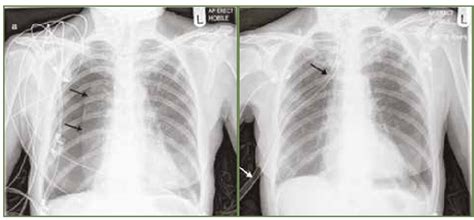

- RTG hrudníku: Obyčajná RTG snímka hrudníka môže odhaliť hiátovú herniu.

- RTG s kontrastnou látkou: Vyšetrenie rozlíši jednotlivé typy kýly. Na RTG hrudníku možno vidieť žalúdočnú bublinu v mediastine. Pri diagnostike je vždy potrebné zistiť, kedy sa bolesť a nepríjemné pocity objavujú. Robí sa špeciálne röntgenové vyšetrenie, pri ktorom sa sleduje prehĺtací akt. Pacient zje kašu, ktorá obsahuje kontrastnú látku a je dobre viditeľná na röntgene - tým sa sleduje prechod značenej potravy tráviacim traktom.